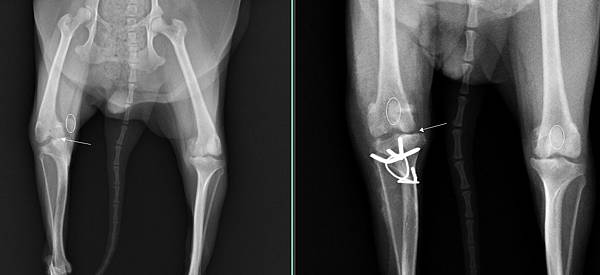

檢查發現嚴重的四級膝蓋股異位

經過醫療團隊努力後

成功的校正